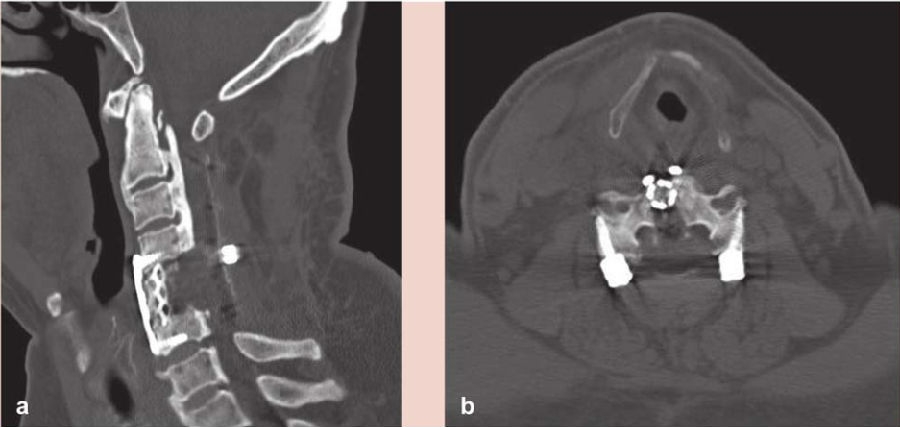

术前CT检查提示颈椎生理曲度变直,C1-7椎体边缘骨质变尖,寰枢间隙变窄(图1左)。C2-6段后纵韧带可见条形骨质密度影,C2-6段椎管有效前后径变窄,最窄处前后径约4mm(图1右)。寰枢关节周围韧带、C2-3段及C5-6段前纵韧带区可见条片状致密影。

图1 术前CT矢状位示颈椎生理曲度变直,后纵韧带钙化明显;

术前CT轴位示椎管前后径变小

术后患者感右手环指及小指肌力较术前提高。复查磁共振(MRI)及CT示C4-6脊髓前方压迫缓解,脊髓形态良好(图6),钛笼位置满意(图7)。

图7 术后CT示钛笼位置良好

a. 冠状位;b.轴位

该病例从术前CT看OPLL严重程度超过椎管横径2/3(图1右),我们首先选择了后路C2-6去椎板减压和侧块内固定术(图2),术后患者四肢肌力改善,神经功能症状得以改善。从术后磁共振(MRI)看(图4),尽管OPLL对脊髓的压迫来自前方,但后路去椎板减压和侧块内固定后,脊髓前方蛛网膜下腔有所改善且明显增宽。术后四肢运动功能改善良好,但患者仍存在C5-6神经根轴位受压和牵拉的疼痛症状,分析确定后,再行C4-6前路ACCF减压。我们对该严重OPLL病例,通过先后路减压+固定的方法,再行前路部分节段减压+固定的方法,既降低了严重OPLL减压手术的风险,又提高了治疗效果。